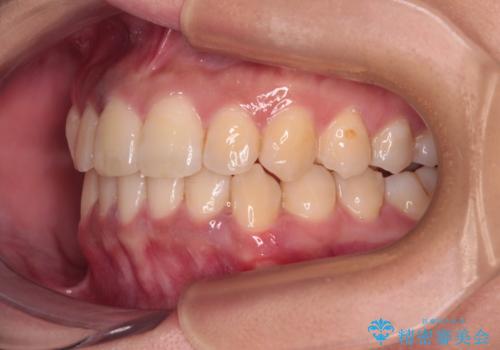

前歯のデコボコと隠れてしまう下顎前歯 インビザラインですっきりと改善

- 前歯のデコボコと、深い咬み合わせにより前歯が隠れていることを気にして来院された患者様です。

海外に長期滞在する予定があるとのことで、インビザラインにて矯正治療を行うこととしました。

インビザライン発注後に長期滞在先から2年間ほど帰国することができず、インビザラインの有効期限内に終了できるのか不安でしたが、矯正治療開始後は十分な装着時間を達成され、1年未満の期間で無事に終えることができました。